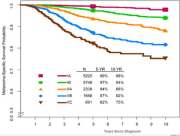

| 06:08, 31 באוקטובר 2023 | Myocarditis3.jpg (קובץ) |  |

130 קילו־בייטים | Motyk | 1 | |

| 14:51, 30 באוקטובר 2023 | Myocarditis2.png (קובץ) |  |

64 קילו־בייטים | Motyk | 1 | |

| 13:08, 30 באוקטובר 2023 | Myocarditis1.png (קובץ) |  |

235 קילו־בייטים | Motyk | 1 | |

| 12:06, 30 באוקטובר 2023 | Myocarditis4.jpg (קובץ) |  |

142 קילו־בייטים | Motyk | 1 | |